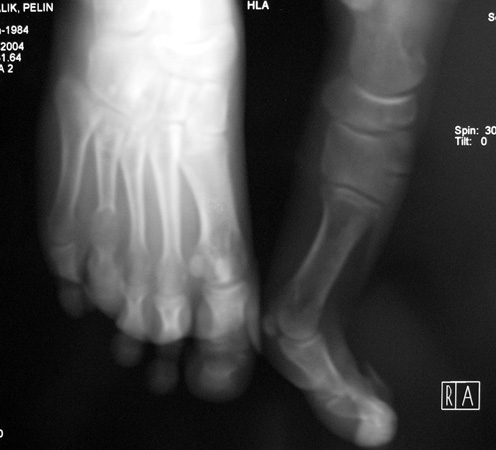

Finger (metacarpus) and toe (metatarsus) shortness can be seen congenitally as a single deformity or as a part of various syndromes; or after trauma or Freiberg disease (avascular necrosis). The frequency of congenital metacarpal or metatarsal shortness is less yhan 1/1000. It is seen 5 times more freqently in women and usually (72%) bilateral. Fourth finger is the most frequently involved. Although the cause of this problem is not known exactly, it is believed that the deformity is usually caused by early closure of the growth plate.

Surgical treatment may be required for metacarpal shortness because of cosmetic disturbance and fatigue in the dominant hand; and for metatarsal shortness because of cosmetic appearance, metatarsalgia, deformity due to dorsal shift of the short finger, pain and pressure ulcers due to plantar shift of the short finger, or difficulty in shoe wearing. Various techniques have been defined for the treatment of congenital metacarpal or metatarsal shortness. However, the most frequently used methods are acute lengthening with grafting, and distraction osteogenesis (callotasis). Callotasis method is preferred for lengthening more than 1 cm. In our department, we prefer distraction osteogenesis with unilateral or circular external fixator for lengthening of metacarpal and metatarsal bones.